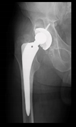

The guiding wire was inserted and controlled with fluoroscopy flashes (Figure 4). The drilling and reaming were carried out in accordance with the recommendations:

Figure 4.

The biocompatible aiming device after insertion of the guiding wire.

The radiological examination allowed us to verify the close bone-to-implant contact and the unchanged position of the implant during follow-up.

In all the cases operated with the above-described targeting procedure, the stems of the cups remained between the cortical bone surfaces without perforation of the linea terminalis, as shown by postoperative radiographs. There were no complicated surgical situations. In 16 cases, the wound healings were uneventful, and the hips were able to bear weight again after postoperative rehabilitation.